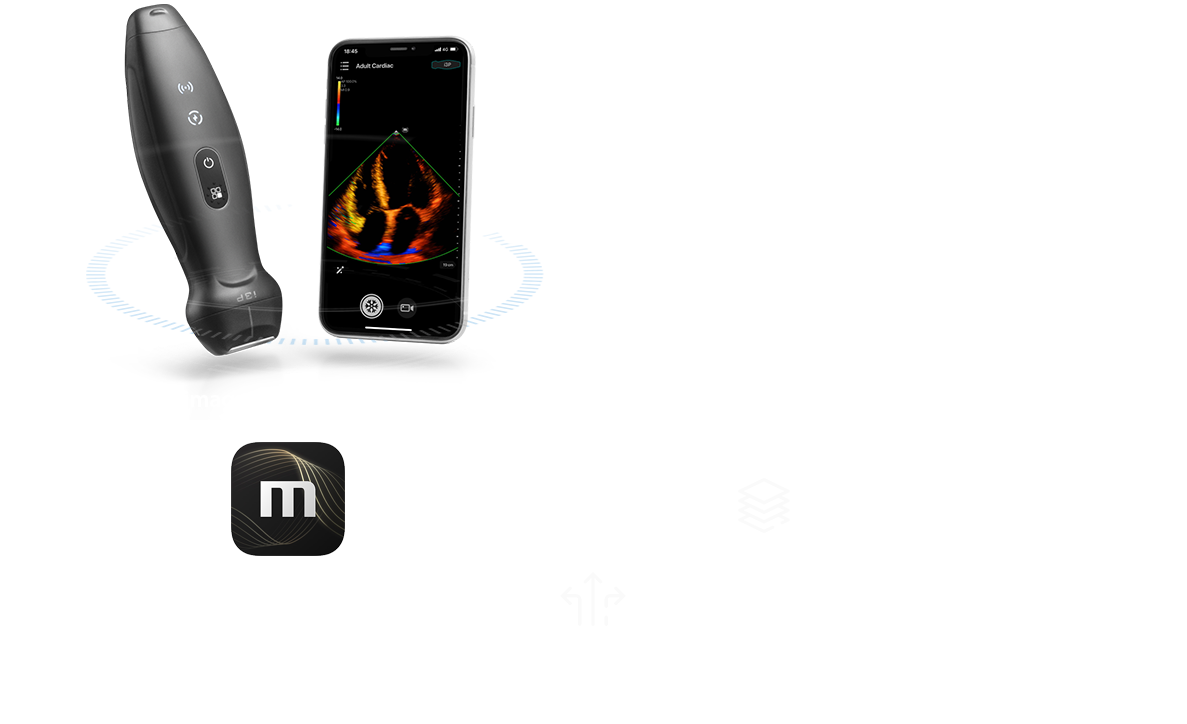

Sistema ecografico portatile wireless

TE Air i3P

TE Air i3P, il sistema ecografico portatile wireless di nuova generazione di Mindray, أ¨ stato progettato per soddisfare questi requisiti clinici piأ¹ elevati, come quelli relativi alle urgenze e alle cure critiche. Coniugando funzionalitأ premium con un'esperienza wireless, una connettivitأ efficiente e un design robusto per ambienti imprevedibili, il sistema ecografico portatile wireless TE Air i3P contribuisce a migliorare la fiducia e l'efficienza dei medici in modi completamente nuovi.

TE Air i3P, il sistema ecografico portatile wireless di nuova generazione di Mindray, أ¨ stato progettato per soddisfare questi requisiti clinici piأ¹ elevati, come quelli relativi alle urgenze e alle cure critiche. Coniugando funzionalitأ premium con un'esperienza wireless, una connettivitأ efficiente e un design robusto per ambienti imprevedibili, il sistema ecografico portatile wireless TE Air i3P contribuisce a migliorare la fiducia e l'efficienza dei medici in modi completamente nuovi.